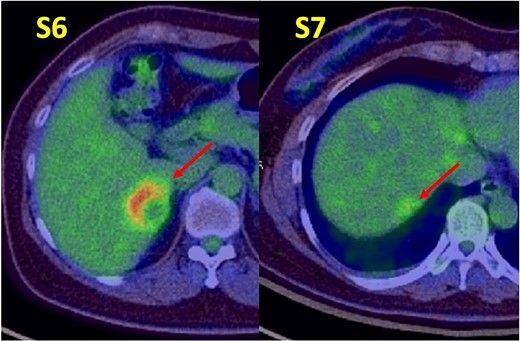

A 52-year-old woman was admitted to our hospital for the evaluation and treatment of multiple cystic liver tumors. Two years earlier, dynamic computed tomography (CT) had detected multiple cystic tumors in segments 6 (S6) and 7 (S7), which were subsequently monitored (Fig. 1a). The patient showed no symptoms; laboratory tests for tumor markers such as α-fetoprotein, protein induced by vitamin K absence or antagonist-II, carcinoembryonic antigen, and carbohydrate antigen 19–9 were within normal ranges. Dynamic CT identified two low-density tumors with peripheral enhancement in the portal phase, featuring cyst-like internal septa (Fig. 1b), which showed slow enlargement over 2 years. Magnetic resonance imaging (MRI) using gadoxetic acid (gadolinium-ethoxybenzyl-diethylenetriamine pentaacetic acid; EOB Primovist®) revealed that tumors appeared as low intensity signals on T1-weighted imaging and high intensity signals on T2-weighted imaging and diffusion-weighted imaging. Additionally, a 7-mm lesion was observed at the S7/8 boundary (Fig. 2a and b). Positron emission tomography-CT (PET-CT) showed abnormal uptake in S6 and S7 tumors but not in the S7/8 lesion (Fig. 3). CT during hepatic arteriography (CTHA) demonstrated well-contrasted tumors at the periphery, with no contrast enhancement in the center (Fig. 4a). Moreover, CTHA detected a new tumor in S8, displaying clear and uniform contrast but not visible with other imaging modalities (Fig. 4b).

Positron emission tomography-computed tomography findings. Abnormal tracer accumulation are observed in the S6 and S7 tumors.